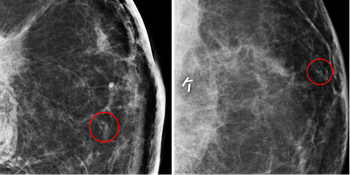

Research provides evidence for imaging mastectomy site during opposite-breast cancer screening.